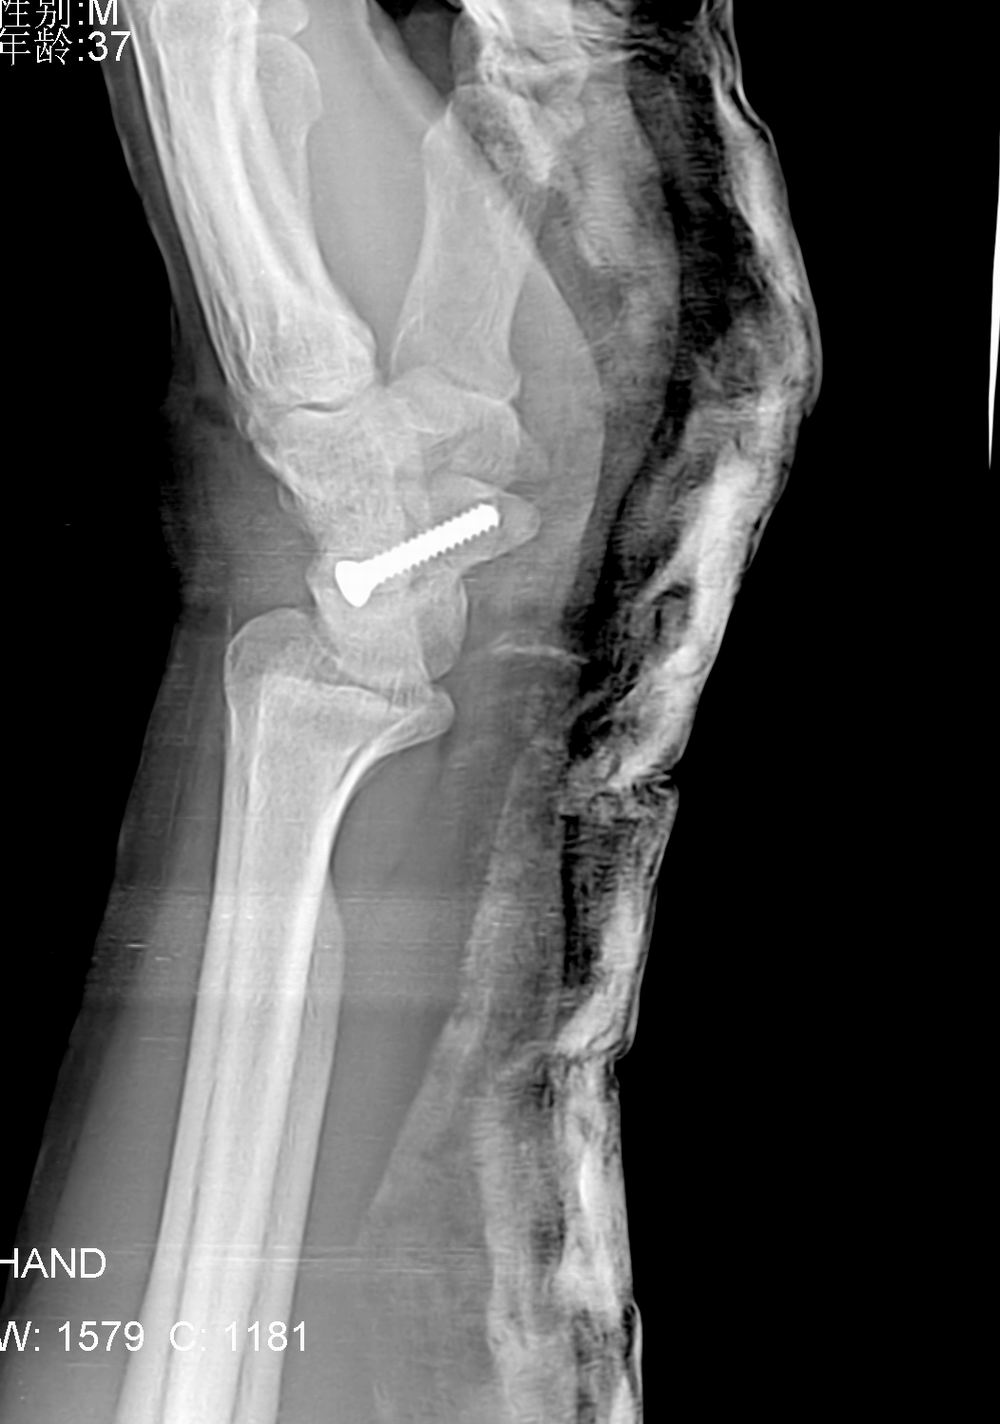

标题: X5107 :舟骨骨折

病人来的时候由于韧带砍断了,体位不正,在接韧带时发现舟骨有骨折,做了手术。

术后片如下: